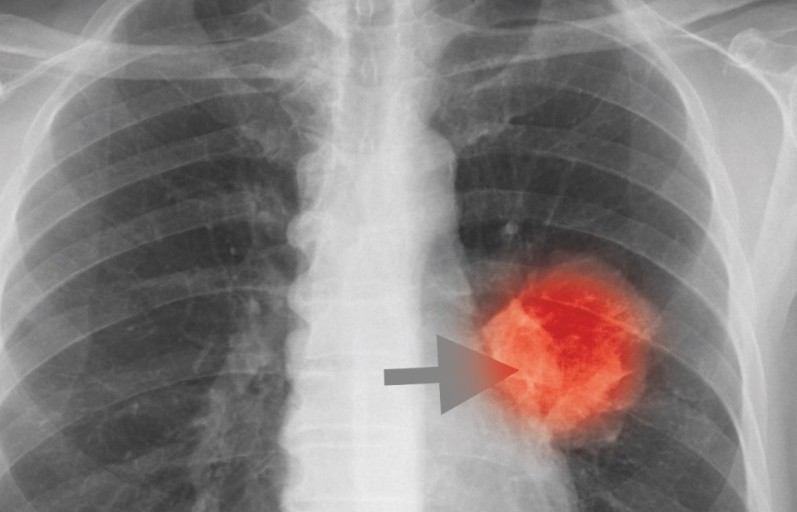

폐렴 증상을 겪는 그럴 경우 X선 촬영 및 배양 검사로 진단할 수 있어요. 필요에 따라 소변, 혈액, 혈청 검사, CT 등을 추가로 실시해요. 폐렴 진단을 받은 환자는 일반적으로 입원을 권장하지 않지만 젊거나 기초질병이나 호흡곤란이 심한 그럴 경우, 고령, 임신 등의 그럴 경우 전문기관에 방문해서 상황에 맞는 신속한 치료와 상태 개선, 위험예방을 받는 것이 좋아요. 폐렴 증상의 치료에서 가장 주요한 것은 항생제로 원인균을 제거하는 것인데요. 세균이나 바이러스 감염에 의해 발생하며 처음에는 항바이러스제를 통해 감기처럼 치료하기도 해요.

폐암 초기증상 11가지 특징

폐암은 위암, 갑상선암 다음으로 3번째로 발병 빈도가 높은 3대 암 중 한 가지인데요. 폐암은 재발과 전이까지의 빈도도 잦은지라 완치가 어렵다고 하며 폐암 발병 초기에는 거의 증상이 없을 수